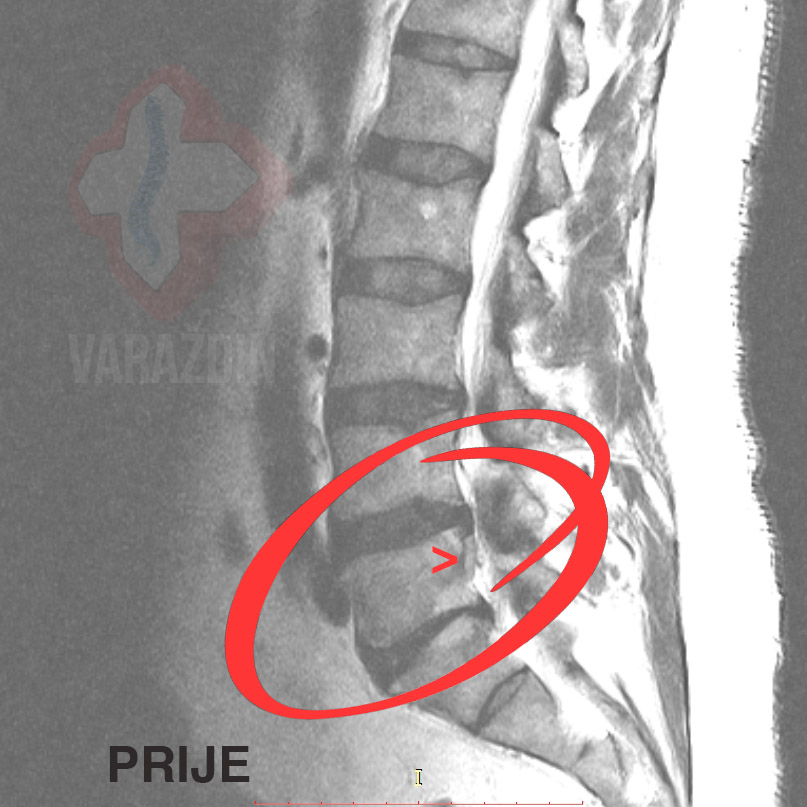

Primjer 1

Klijent se javlja u Nado centar sa snimkom na kojoj je

vidljiva sekvestacija diska. Kod klijenta je prisutna bol u

križima preko lijevog gluteusa duž lijeve noge uz lagane trnce u

potkoljenici. Nakon konzultacija i utvrđenog optimalnog tijeka

liječenja, klijentu se kroz 15 dekompresijskih

tretmana sekvestar razgradio.